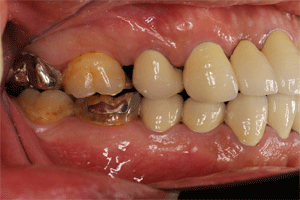

初診からやく6年たちました。少しは歯肉縁上の部分が磨けるようになってきました

この1年ちょっとの間に、かなりの介入がありました。   5本の歯が抜歯になり、補綴をおこなっています。   右上の1番抜歯、ここは6本のブリッジを作り直しています。前回まで、ヒビが入っていましたが、気にならないとのことなので、そのままでしたが、抜歯を期に新製しました

右上の7は抜歯をして、そのままの状態にしています

右下6と7は抜歯して、義歯を新製、左下5は抜歯して、ブリッジを作っています。抜いて欲しいとなるまで、がんばったのですが、このような結果となりました。少しでも抜歯の時期が遅れて、患者さんは満足されています。炎症の部位は42カ所、4ミリ以上のポケットは34カ所、減少するようにがんばっていきます 歯を抜きたくない 2010年 はこちらをクリック  |